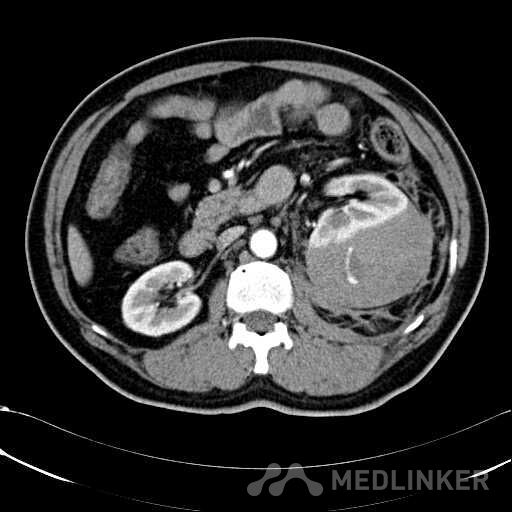

患者是54岁男性 主 诉: 突发左腰部疼痛3小时。 现病史: 缘于入院前3小时患者无明显诱因出现左腰部剧烈疼痛,无向他处放射,与活动及体位无明显关系,伴有腹胀、恶心、呕吐,无头痛、头晕,无人事不省、口吐白沫,无胸闷、胸痛、咯血,无发热、畏冷、寒战,大小便未解,肛门无停止排气,遂就诊我院,查“泌尿系彩超:左肾实质及不均质回声区,范围约9.4*4.1cm,界不清,内未见明显血流信号”,为进一步治疗,门诊拟“左肾占位”收住入院,发病以来,患者精神欠佳,未进食,大小便如前述,体重无明显改变。 患有“高血压病”7年,规则服药治疗(具体不详),监测血压情况不详。 T: 36.5 ℃ P: 65 次/分 R: 20 次/分 BP: 154/94 mmHg 双肾区皮肤无红肿、破溃及隆起,双肾肋下均不能被触及,左侧肾区叩击痛明显,右侧肾区无叩击痛,双侧肾区未闻及血管杂音。膀胱区无隆起,无压痛,耻骨上膀胱区叩诊空虚。外生殖器发育正常。 2016-04-12 泌尿系彩超:左肾实质及不均质回声区,范围约9.4*4.1cm,界不清,内未见明显血流信号。 04-12血常规:血红蛋白 151 g/L,白细胞 16.80 10^9/L,中性粒细胞百分比 84.90 %。急诊生化:白蛋白 39.8 g/L,葡萄糖 9.46 mmol/L。